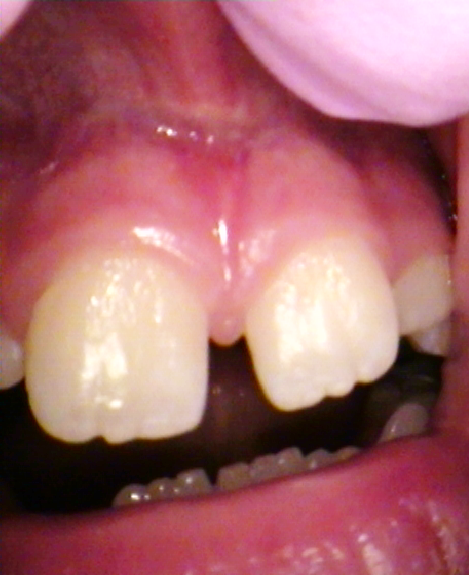

zabiegi stomatologiczne wędzidła – laser stomatologiczny